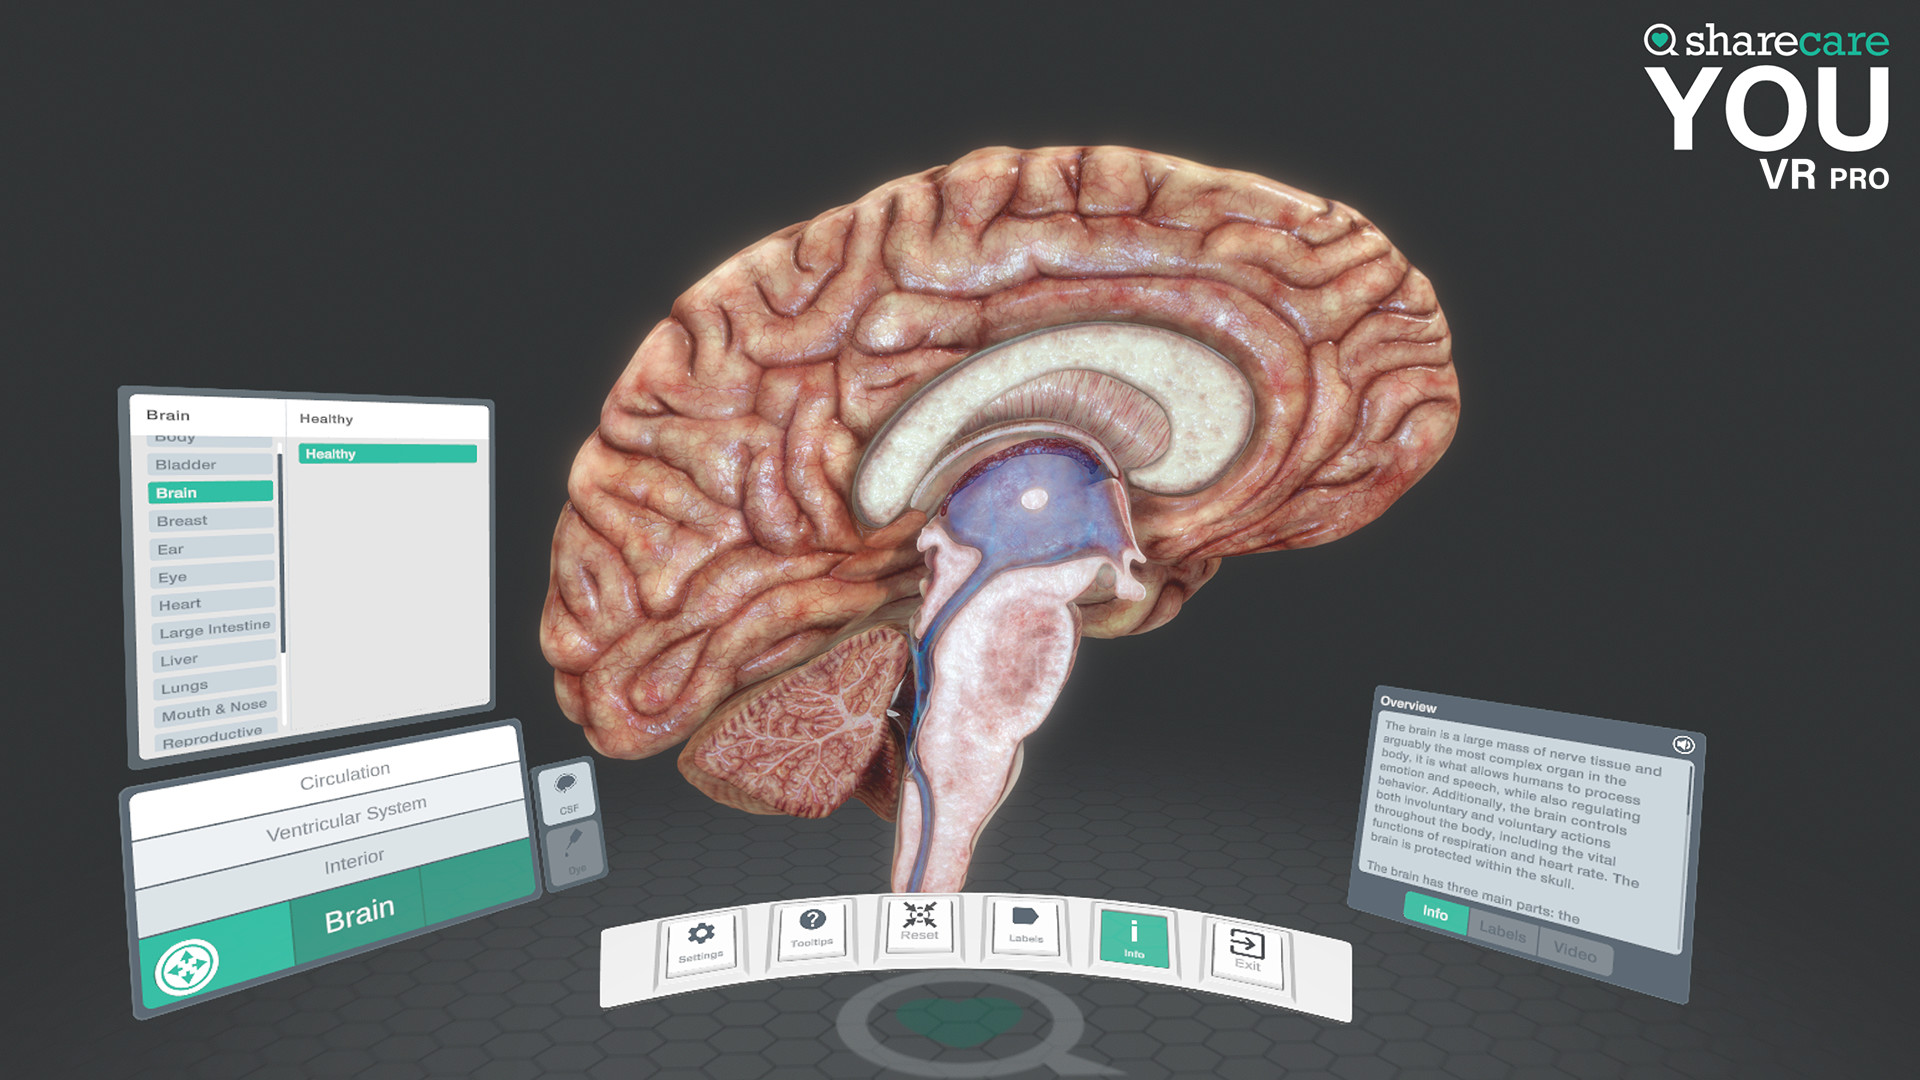

The winner of the 2019 Appy Best VR App is now available on Mac and PC, with more content, bolder graphics, and enhanced features! Sharecare YOU VR is a fully immersive, photorealistic simulation of the human body, enabling anyone to explore its astonishing details in full 360 degrees. Interested in learning about a specific organ? With the click of a button, travel inside, visualize its natural function, and dive deeper. Want to learn even more? Check out the many tags and labels along the way to gain even more information and insight. Easily customize YOU to better understand physiology and simulate disease. You can even personalize our avatars to be a virtual you – your health, your conditions. It really is all about YOU. With YOU VR PRO, users can create visually compelling, high-quality educational content. Build YOU lectures and presentations easily, with the help of video and voiceover recording, and the ability to draw and add your own text. You can also be the star within these videos using our web-cam feature.

- YOU content - an expanding library of over 40 different scenes to explore including anatomy, physiology, conditions, and treatments

- Informative labels and scene information

- Completely updated user interface with unique interactive controls

Looking to use the content for Business Purposes? Get the Sharecare YOU VR Pro version and have the ability to use all the amazing content for Business Purposes. Take advantage of breathtaking graphics and never seen before views of the human body. Your ability to better communicate human anatomy and physiology with your customers and/or students is at your fingertips!